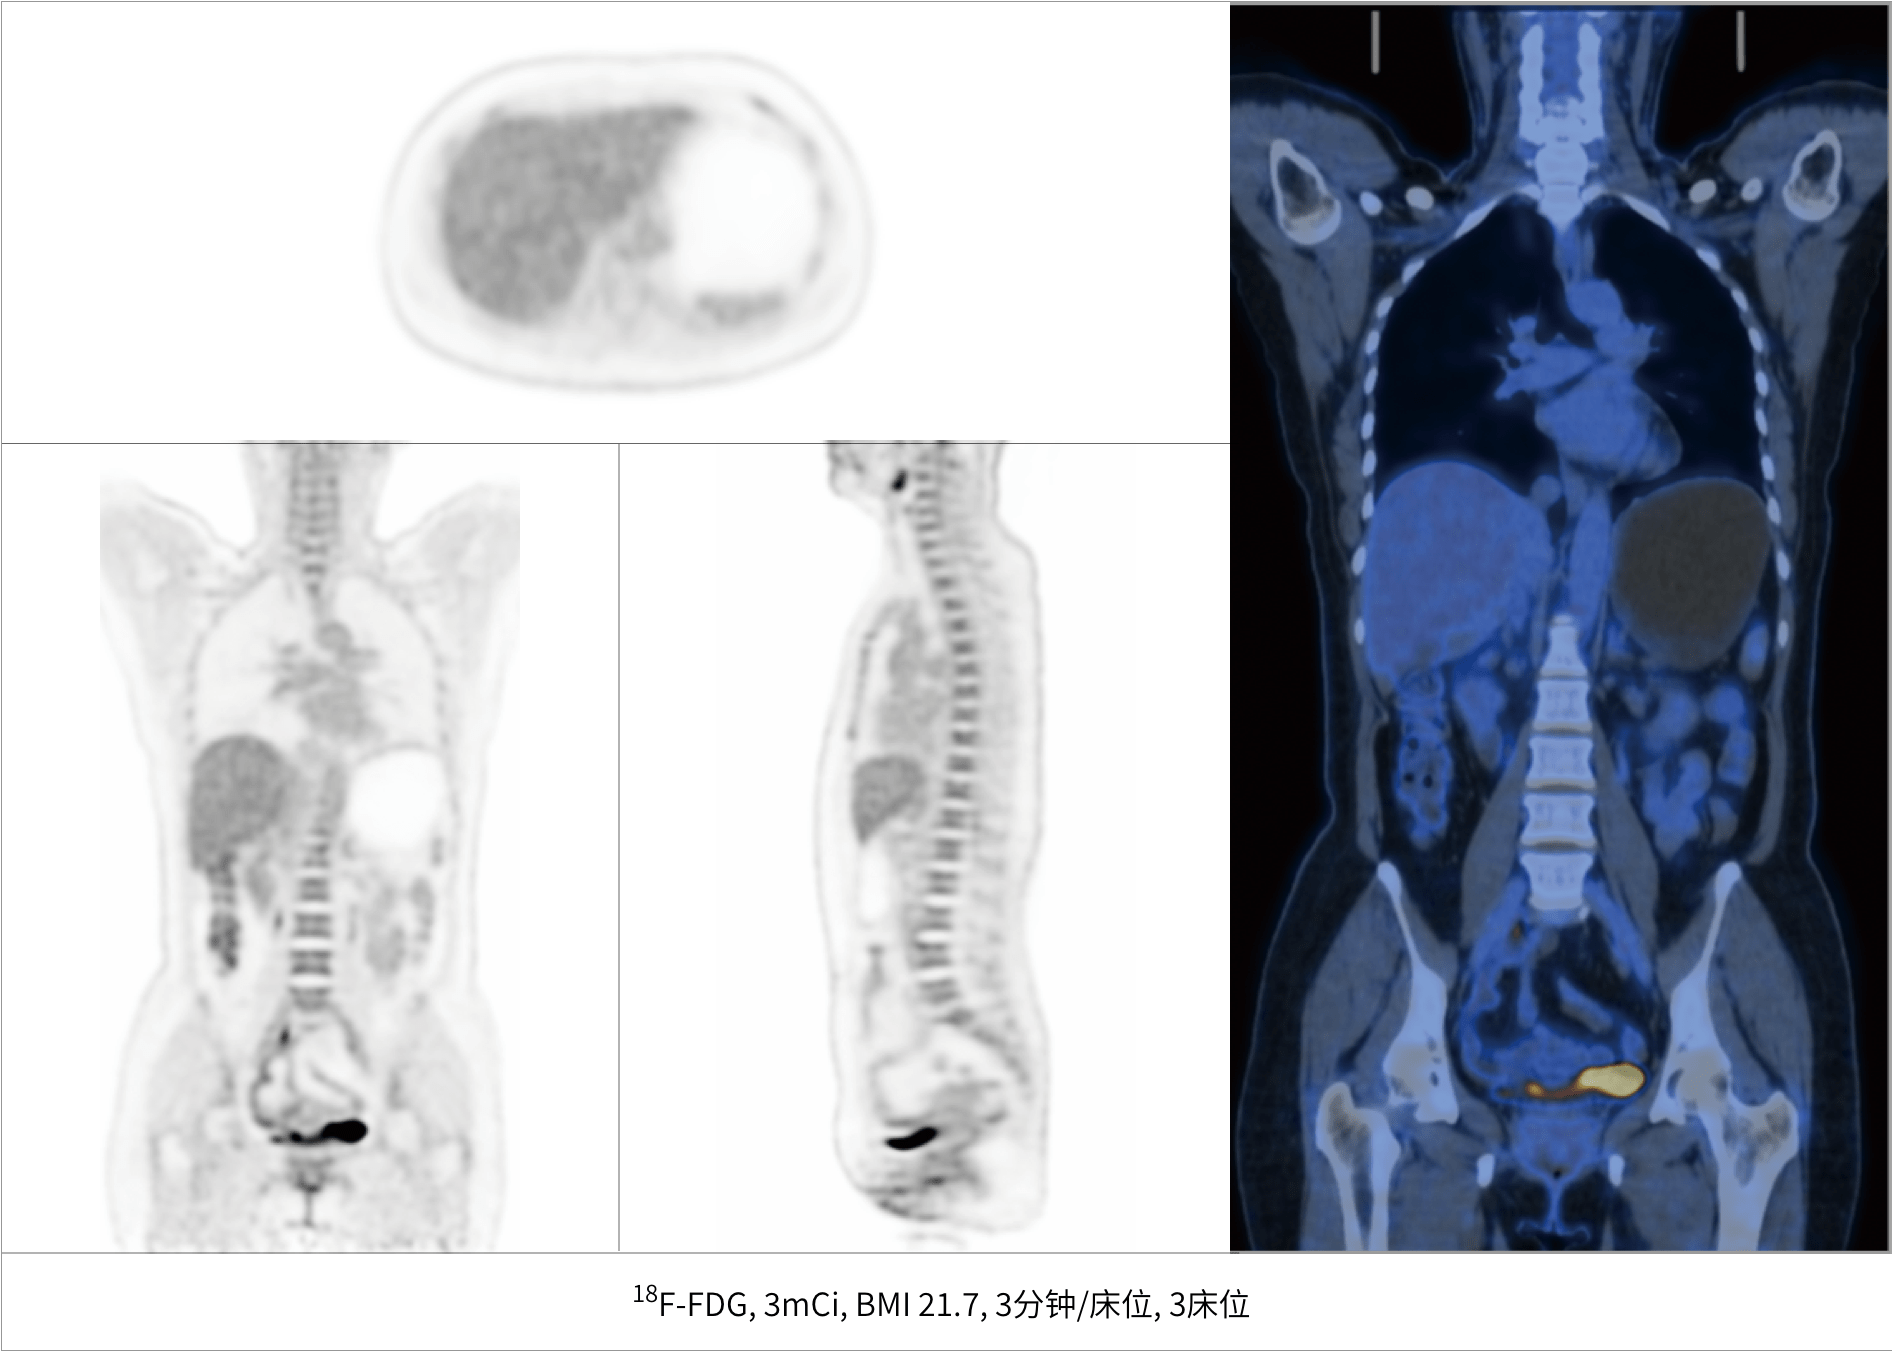

超清显像

2.9mm

超清NEMA分辨率成像

TOF + PSF

微小病灶无以遁形

600 x 600

超大矩阵,高精度超清重建